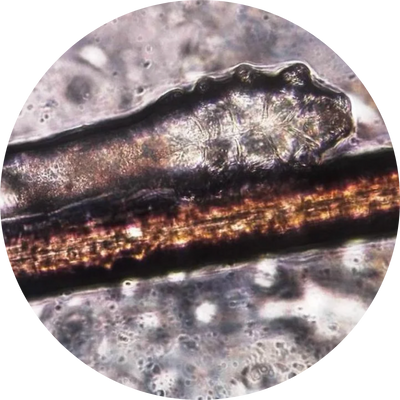

Mectin Labs Rosacea Cream targets the root cause of redness, irritation, and flare-ups Demodex mites. These microscopic parasites live inside pores and hair follicles, where they cause inflammation, itching, and rosacea outbreaks.

Mites Are Invading Your Skin!

They don’t just sit on the surface they live deep inside your pores and follicles, fueling redness, irritation, and rosacea flare-ups.

Here’s how Demodex mites cause damage and why eliminating them with Mectin Labs Ivermectin 1% Cream is so important:

Demodex folliculorum

Causes

Overgrowth in facial hair follicles

Excess oil, dead skin buildup

Risks

Facial redness

Rosacea flare-ups

Scaly or rough skin texture

Demodex brevis

Overgrowth in sebaceous (oil) glands

Weakened skin barrier

Itching & burning

Acne-like breakouts

Inflammation deep in pores